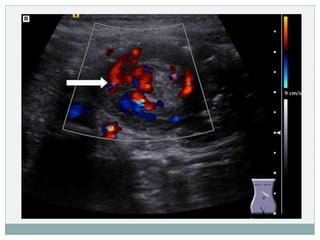

 ECO:

 Método de elección.

 S y E cercanas al 100%. VP – cercano al 100%.

 Signo en ‘ojo de buey’ o ‘donut’.

 Doppler: falta de flujo en la zona invaginada

DIAGNÓSTICO (TÉCNICAS DE IMAGEN) ECO:  Método de elección.  S y E cercanas al 100%. VP – cercano al 100%.  Signo en ‘ojo de buey’ o ‘donut’.  Doppler: falta de flujo en la zona invaginada  ENEMA OPACO:  Método diagnóstico – terapéutico.  Signo del ‘muelle enrollado’  1ª elección cuando hay diagnóstico claro ( Formas típicas).